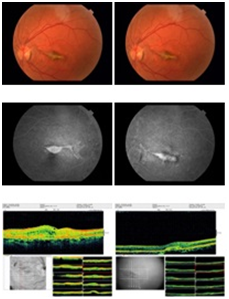

Initial mean central retinal thickness was 477.3 μ (range 776-363 μ) and decreased to 277.5 μ (range 223 – 467 μ) at the last visits. Mean central retinal thickness reduction was 199.8 μ (range 84-541 μ). Complete resolution of intra and/or subretinal fluid on OCT occurred in four eyes (66.8%). In two eyes which two injections were performed (33.2%), intra and/or subretinal decreased but never completely disappeared. Angiographic leakage was completely resolved in six eyes (100%) (Figure 2). No ocular or systemic complications such as endophthalmitis, retinal tear, retinal detachment, uveitis, myocardial infarction or cerebrovascular accidents were noted. Data of the patients are shown in Table 1.

Figure 2 After anti VEGF injection: Fundus photograph of patient 1 showing decrease choroidal neovascular membrane due to angioid streaks. Fluorescein angiography shows decrease in classic subfoveal choroidal neovascular membrane with leakage. OCT shows decrease in subretinal edema.